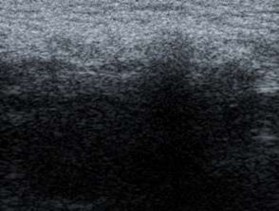

Hình 3.3. Hình ảnh siêu âm mô xơ ở vùng bẹn phải, xuất hiện đường tăng âm với bóng đen cản âm ở phía sau. Bệnh nhân: Lê Nh. 67 tuổi, Nam.

Bảng 3.27. Phân bố độ dày mô xơ của tấm lưới dưới siêu âm

Số trường hợp | Tỉ lệ (%) | |

Mô xơ dày | 121 | 100 |

Mô xơ mỏng | 0 | 0 |

Tổng | 121 | 100 |

Độ dày mô xơ | 2,51 ± 0,21 mm | 2,1 - 3,5 mm |

Bảng 3.28. Phân bố vị trí tấm lưới dưới siêu âm

Nằm ngay ống bẹn | 121 | 100 |

Di lệch, di chuyển | 0 | 0 |

Mô xơ tạo thành quanh tấm lưới nằm ở vùng bẹn 100%, không có di chuyển và di lệch.